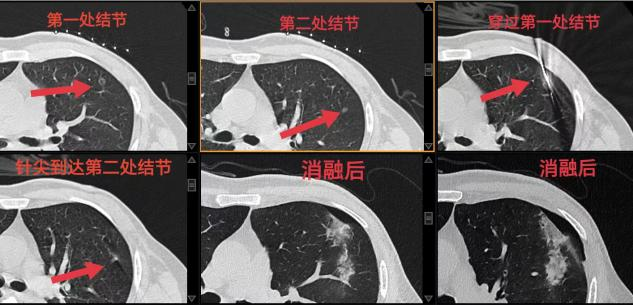

患者入院完善術前檢查后,經肺結節MDT討論確認劉女士有手術指征。由于患者表示不愿做外科手術,呼吸介入團隊與患者及家屬充分溝通后,決定為其行CT引導下左上肺結節微波消融術。手術過程順利,呼吸介入團隊胡學進副主任醫師用精湛的技術使用一根消融針進行穿刺,以非共面的形式用消融針先穿過第一個結節,再穿刺至第二個結節,用一根消融針一次性突破兩個肺結節病灶并分別進行消融,做到了“一箭雙雕”,避免了多處多次穿刺導致氣胸、出血等并發癥的發生,同時也為患者節省了費用。患者術后恢復良好,對手術效果非常滿意。

王開金副主任介紹,在CT引導下肺結節消融治療術具有微創、精準定位、安全性高、術后恢復快等優點,目前已經成為解決多發肺結節的首選方案之一。我院呼吸與危重癥醫學科目前已經常規開展肺結節及肺癌的微波消融、射頻消融、氬氦刀冷凍消融等多種消融治療,將為更多肺結節、肺癌患者帶來新選擇和新希望。